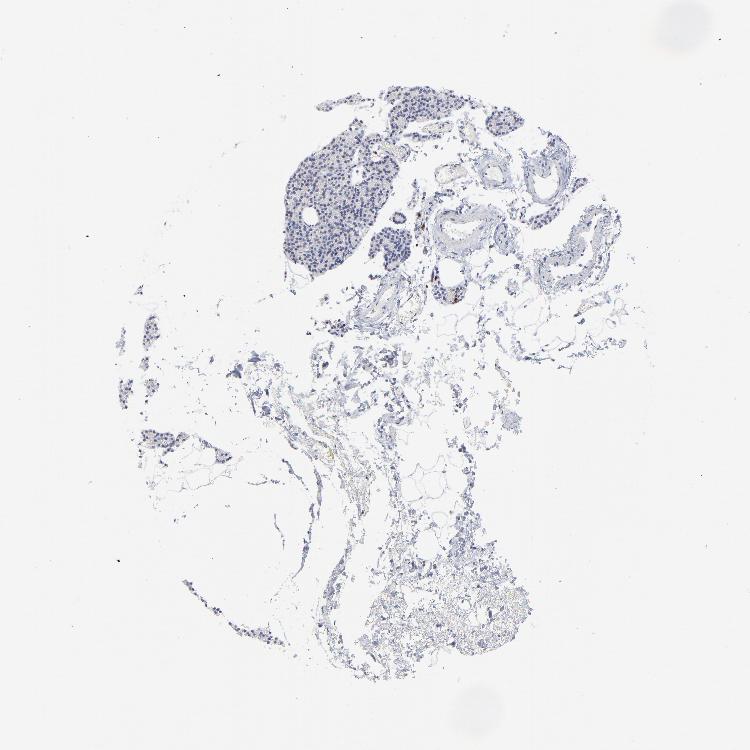

PARATHYROID GLAND - Antibody stainingi

Antibody staining in the annotated cell types in the current human tissue is reported as not detected, low, medium, or high, based on conventional immunohistochemistry profiling in selected tissues. This score is based on the combination of the staining intensity and fraction of stained cells.

Each image is clickable and will lead to virtual microscopy that enables deeper exploration of all samples and also displays staining intensity scores, fraction scores and subcellular localization as well as patient and tissue information for each sample.

Antibody HPA003134Antibody CAB002625

Glandular cells Not detectedLow